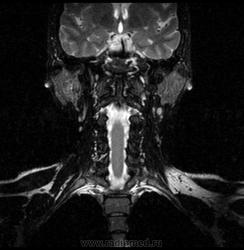

06.06.2011 МРТ - головы и шеи.

Пацентка 36 лет, с жалобами на припухлось в околоушной области справа.

В глубокой доле  правой околоушной железы  на фоне неизмененной паренхимы зона  гетерогенного по Т2, гипоинтенсивного по Т1  с единичными гиперинтенсивными включениями.При контрастировании- накопление контраста диффузное неоднородное и по периферии.Рискну предположить злокачественное образование ( аденокарцинома) с низкой степенью злокачественности( есть капсула, экспансивный рост).Сильно не расстреливайте.

Проблема в том, что перед челюстно-лицевым хирургом стоит распространенность любого объемного процесса, в данном случае все упирается в возмможную травму лицевого нерва и конечно же с дальнейшим его парезом, а ведь женщина  еще молодая. Образование имеет тонкостенную оболочку, по структуре неоднородно, с наличием кальцината, при этом МР-сигнал от окружающих анатомических структур(как костных так и мышечных) не изменен, т.е. об инфильтративном росте речи не идет, в какой то степени доброкачественное. В конкретном случае лицевой нерв с ретромандибулярной веной просто несколько оттеснен.

По гистологии аденома околоушной слюнной железы, но после удаления пока сохраняется парез лицевой мускулатуры, возможно временный.